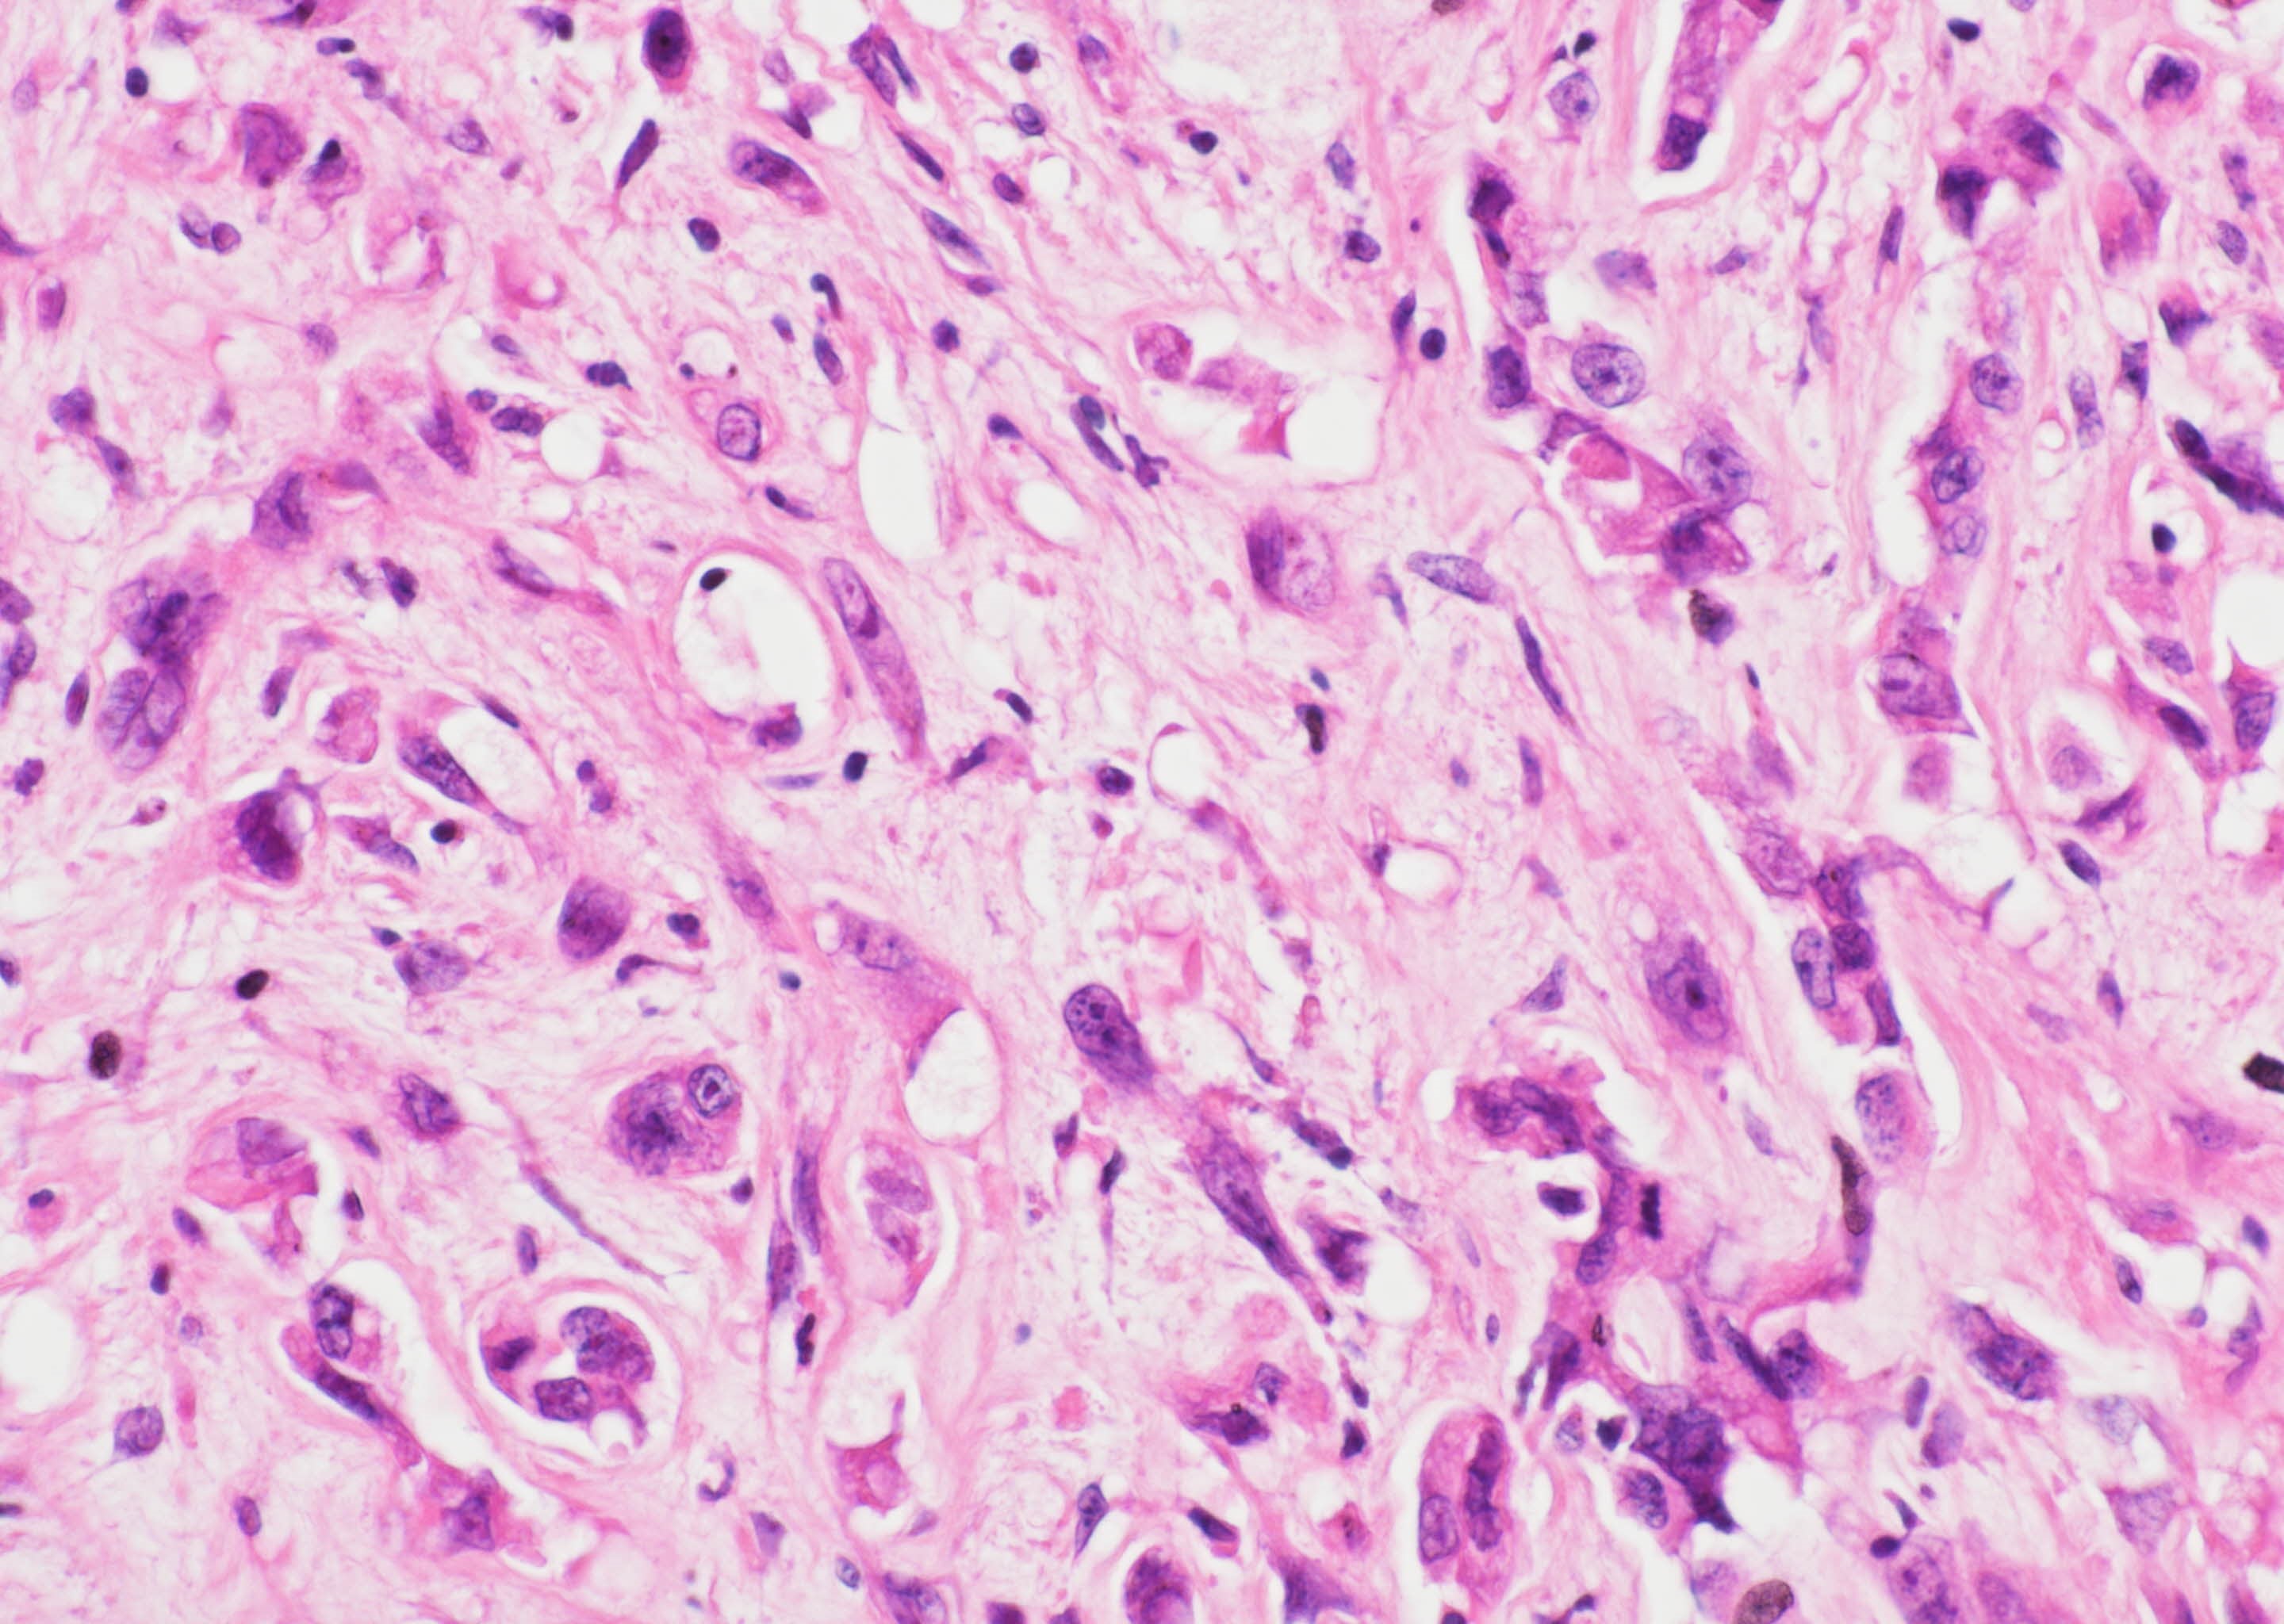

- YAP-TFE3 subtype:

- Solid nests or pseudo alveolar arrangement of epithelioid cells enmeshed in a fibrous stroma

- Tumor cells have abundant, densely eosinophilic cytoplasm and can form vascular spaces

- Intracytoplasmic vacuoles are rare

- Usually minimal mitotic activity, atypia or necrosis

- Up to 10% of cases exhibit frank malignant features of prominent nuclear pleomorphism, increased mitotic activity, solid growth or necrosis; these tumors resemble epithelioid angiosarcoma and have a more aggressive behavior (Am J Surg Pathol 2008;32:924)

Microscopic (histologic) images